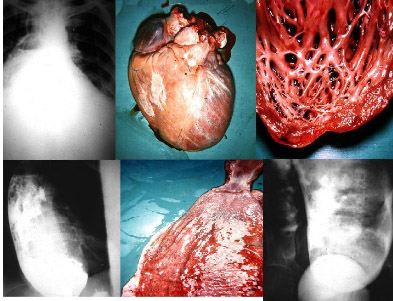

Trong bài viết, chúng tôi có một số thuật ngữ chuyên ngành ký sinh trùng, đặc biệt về Trypanosoma spp, giữ nguyên (tạm không dịch) và chi sẻ với quý bạn đồng nghiệp một số hình ảnh trong Atlas ảnh Trypanosoma spp gây bệnh qua nhuộm giêm sa và chụp dưới kính hiển vi điện tử trích từ internet.